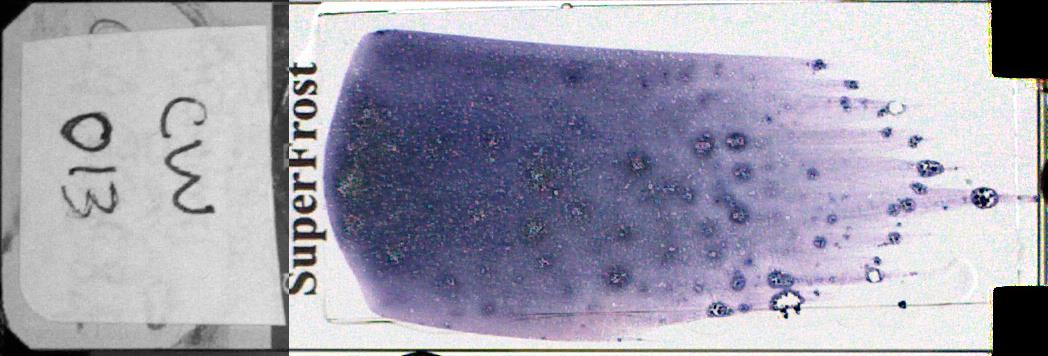

CW013-Normal Bone Marrow Aspirate

MGG